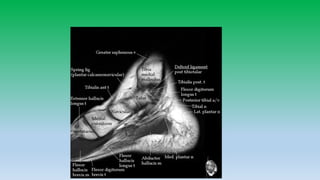

Spring ligament complex:

• Aka calcanio-navicular ligament.

• Is a stabilizer of medial longitudinal arch.

• Has three components based on insertion

on navicular bone

1) Superomedial band: connecting

stanticulum of calcanium to superomedial

aspect of navicular bone. In between

posterior tibial tendon and medial head of

talus.

2) Medioplanter oblique band.

3) Inferoplanter longitudinal band.

Tarsal tunnel :

• Fibro-osseous tunnel located on medial side of ankle and hind foot

extending from medial malleolus to navicular bone.

• Talus and sustentaculum tali forms lateral wall and medially by flexor

retinaculum and abductor hallucis muscle.

• Contents: Posterior tibila N/A/V, tibialis posterior, FDL, FHL tendons.

• Syndrome can arises from abnormalities intrinsic or extrinsic to

tunnel.